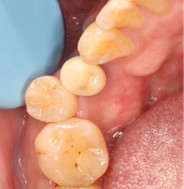

November 23, 2025: Implant follow-up examination. The implant surgical site showed excellent healing, with no abnormal bone density around the implant and satisfactory osteogenesis. The third-stage impression taking was implemented. The panoramic radiograph below confirmed the complete seating of the implant impression coping.

December 4, 2025: Definitive crown delivery. The margin of the implant-supported crown exhibited optimal adaptation.

Pre- and Post-Restorative Comparison